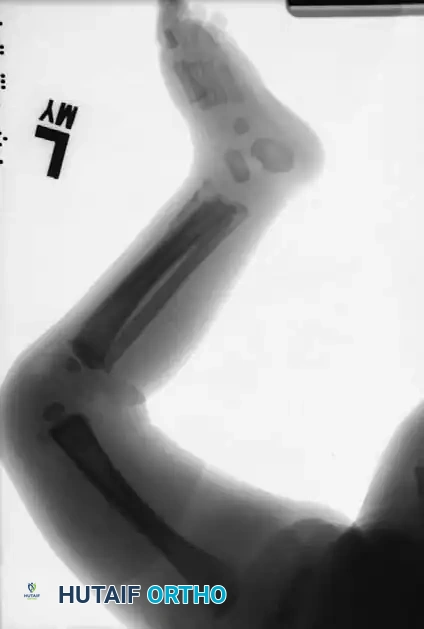

Image

The Role of the Orthopedic Surgeon in NAT

The most common sites of fractures caused by child abuse are the diaphyseal regions of the humerus, tibia, and femur.